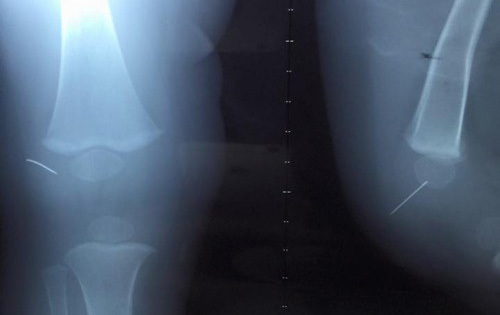

Kim khâu 'chạy' trong gối bé trai 1 tuổi

1/2 cây kim đâm vào đầu gối bé trai nhưng khi mở bao gối, các bác sĩ không tìm thấy đoạn kim nào.